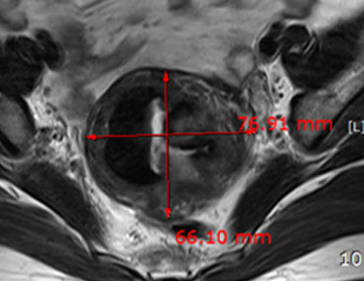

자궁근종 치료 사례

• 시술 전

시술 후